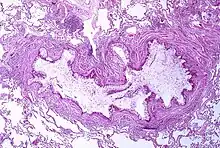

Asthma is the result of chronic inflammation of the conducting zone of the airways (most especially the bronchi and bronchioles), which subsequently results in increased contractability of the surrounding smooth muscles. This among other factors leads to bouts of narrowing of the airway and the classic symptoms of wheezing. The narrowing is typically reversible with or without treatment. Occasionally the airways themselves change.[22] Typical changes in the airways include an increase in eosinophils and thickening of the lamina reticularis. Chronically the airways' smooth muscle may increase in size along with an increase in the numbers of mucous glands. Other cell types involved include T lymphocytes, macrophages, and neutrophils. There may also be involvement of other components of the immune system, including cytokines, chemokines, histamine, and leukotrienes among others.[21]